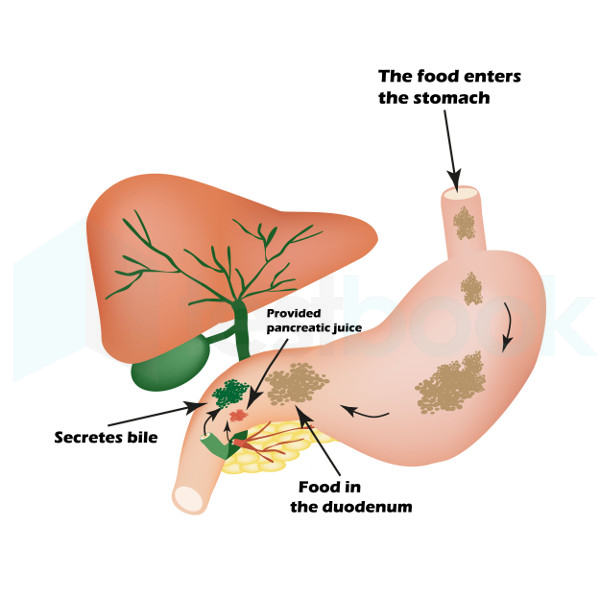

Фотографии медицинских исследований инсулиномы и синдрома Триады Уиппла